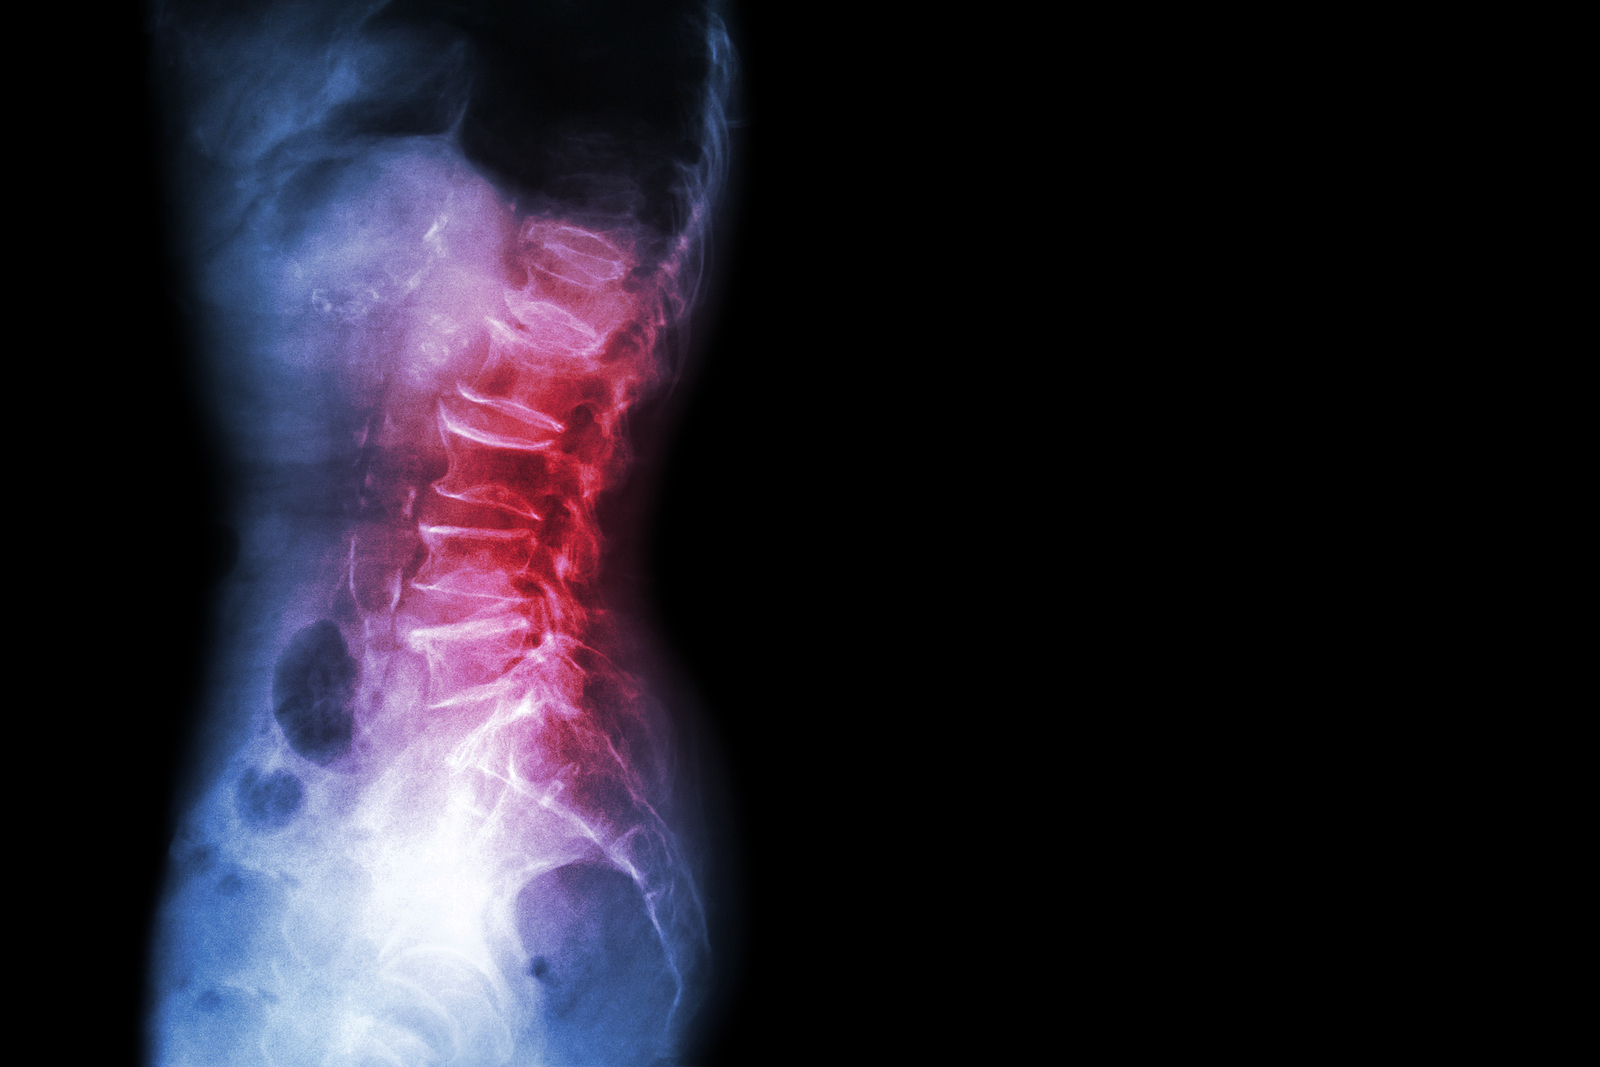

What Makes Up the Lumbar Spine?

The human spine is made up of 24 spinal bones, called vertebrae, as well as the sacrum and the coccyx. The sacrum is a triangular bone near the bottom of the spine and the coccyx is more commonly known as the tailbone.

Vertebrae are stacked on top of one another to create the spinal column. The spinal column gives the body its form and helps sustain an upright position.

The lumbar spine—where pain is often experienced—is made up of five vertebrae positioned near the bottom of the spinal column. Doctors often refer to these vertebrae as levels L1, L2, L3, L4 and L5. The ‘L’ refers to ‘lumbar’. The lowest vertebra, L5, is connected to the top of the sacrum—a triangular bone at the base of the spine that is located between the two pelvic bones. Some people are born with an extra or sixth lumbar vertebra called L6. Having an extra vertebra doesn't usually cause physical problems.

X-rays are usually the first test ordered before any of the more specialized tests are completed. X-rays use electromagnetic radiation to show problems with bones and can also reveal problems such as fractures, infections, or bone tumors. X-rays of the spine can give your doctor information about bone alignment and can demonstrate how much degeneration has occurred in the spine. Both alignment and degeneration can affect the amount of space in the neural foramina and between the discs, which subsequently impacts the nerves in the area. This is important information your health care professional can use to establish a treatment plan.